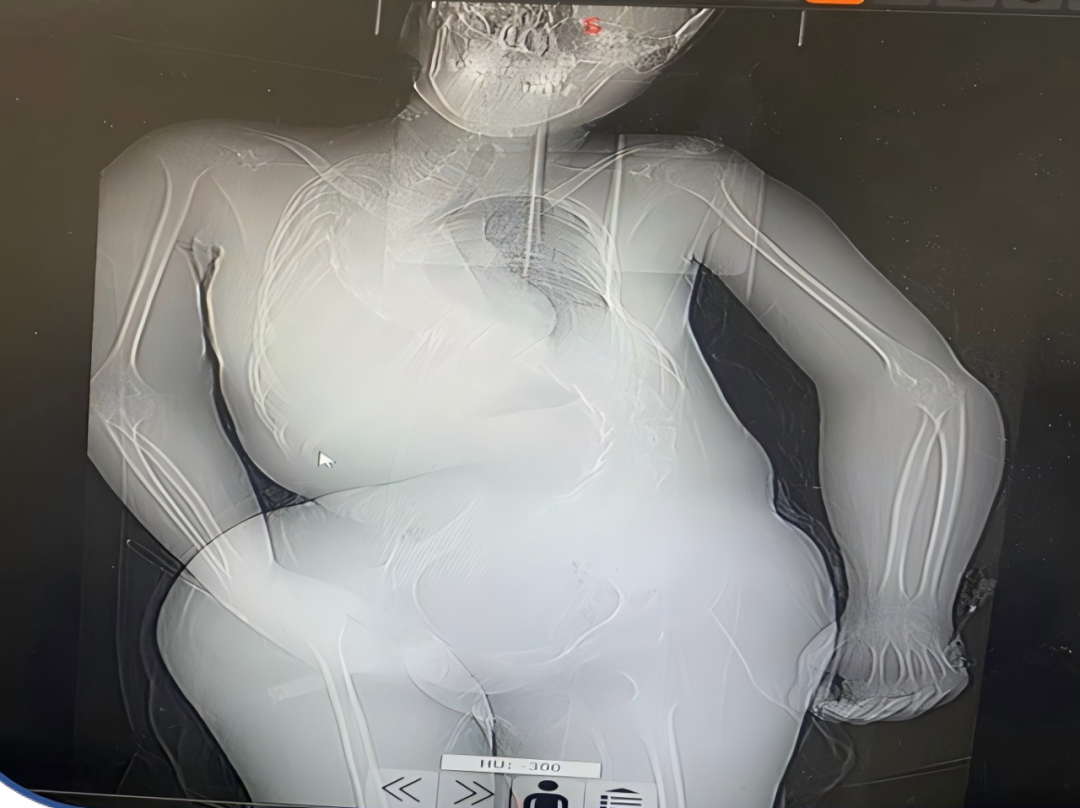

检查结果进一步揭开了病情的严重程度:12 月 26 日胸部 DR 提示支气管肺炎、脊柱 S 型侧弯;12 月 30 日胸部 CT 更是显示右肺支气管闭塞伴右全肺不张、左肺下叶炎症、右侧胸腔积液,头颅 CT 还发现了鼻窦炎。多重并发症叠加,让这个本就患有重症肌无力的孩子,陷入了多脏器功能受威胁的险境。

在医护团队的全力守护下,小西的病情逐渐好转:1 月 5 日复查胸部 CT 显示,两肺炎症较之前明显吸收,右肺也成功复张;心率、血氧、血压等生命体征趋于平稳,不再发热。经过十余天的紧张救治,小西终于达到临床治愈标准,目前已顺利出院。